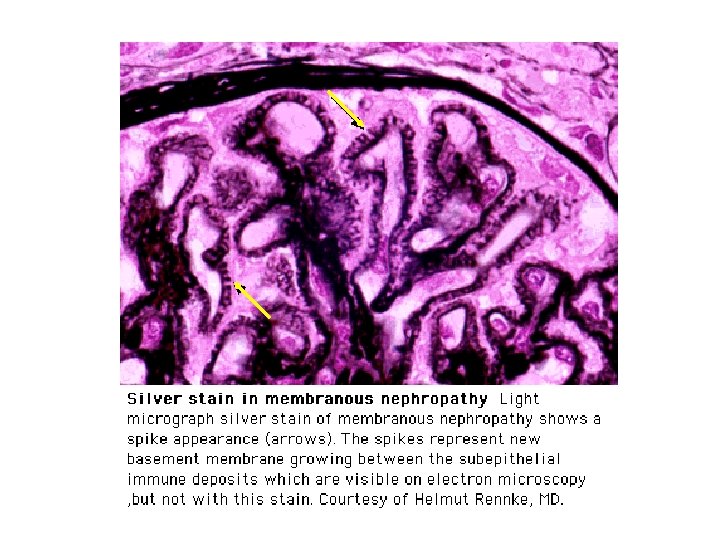

Membranous nephropathy • Aetiology • - usually idiopathic but can be 2 y to drugs, SLE and malignancy in up to 20% cases. Should consider lung, colon and breast cancer in elderly patients • Presentation • - asymptomatic proteinuria or nephrotic syndrome. (MCGN type 2 not membranous is associated with partial lipodystrophy) • Diagnosis • - LM shows uniform thickening of GBM, EM subepithelial humps and IF granular deposition of Ig. G along GBM. Humps are Ag/Ab complexes in the GBM. Their origin is not known. The Ab is not directed at the GBM itself • Treatment • - supportive only unless progressive decline in function (MRC trial) • - no evidence for plasma exchange • Outcome • - 33% stay the same, 33% get better and only 33% develop progressive renal failure

Membranous nephropathy • Aetiology • - usually idiopathic but can be 2 y to drugs, SLE and malignancy in up to 20% cases. Should consider lung, colon and breast cancer in elderly patients • Presentation • - asymptomatic proteinuria or nephrotic syndrome. (MCGN type 2 not membranous is associated with partial lipodystrophy) • Diagnosis • - LM shows uniform thickening of GBM, EM subepithelial humps and IF granular deposition of Ig. G along GBM. Humps are Ag/Ab complexes in the GBM. Their origin is not known. The Ab is not directed at the GBM itself • Treatment • - supportive only unless progressive decline in function (MRC trial) • - no evidence for plasma exchange • Outcome • - 33% stay the same, 33% get better and only 33% develop progressive renal failure

Renal Immunofluorescence and Electron Microscopy • Ig. A nephropathy - mesangial deposition of Ig. A • Lupus - full house IF of Ig. G, Ig. A, Ig. M, C 3, C 4 • Membranous - granular staining for Ig. G along GBM with subepithelial immune complex deposits “spikes” on silver staining • Minimal change - foot process fusion on EM only • AASV - no immunoglobulin deposition - described as pauci immune to distinguish from lupus in patient with crescentic nephritis

Renal Immunofluorescence and Electron Microscopy • Ig. A nephropathy - mesangial deposition of Ig. A • Lupus - full house IF of Ig. G, Ig. A, Ig. M, C 3, C 4 • Membranous - granular staining for Ig. G along GBM with subepithelial immune complex deposits “spikes” on silver staining • Minimal change - foot process fusion on EM only • AASV - no immunoglobulin deposition - described as pauci immune to distinguish from lupus in patient with crescentic nephritis